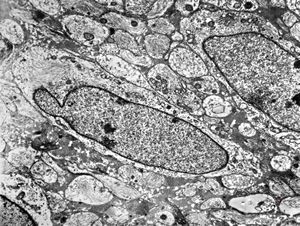

M,10y. | herpetic encephalitis